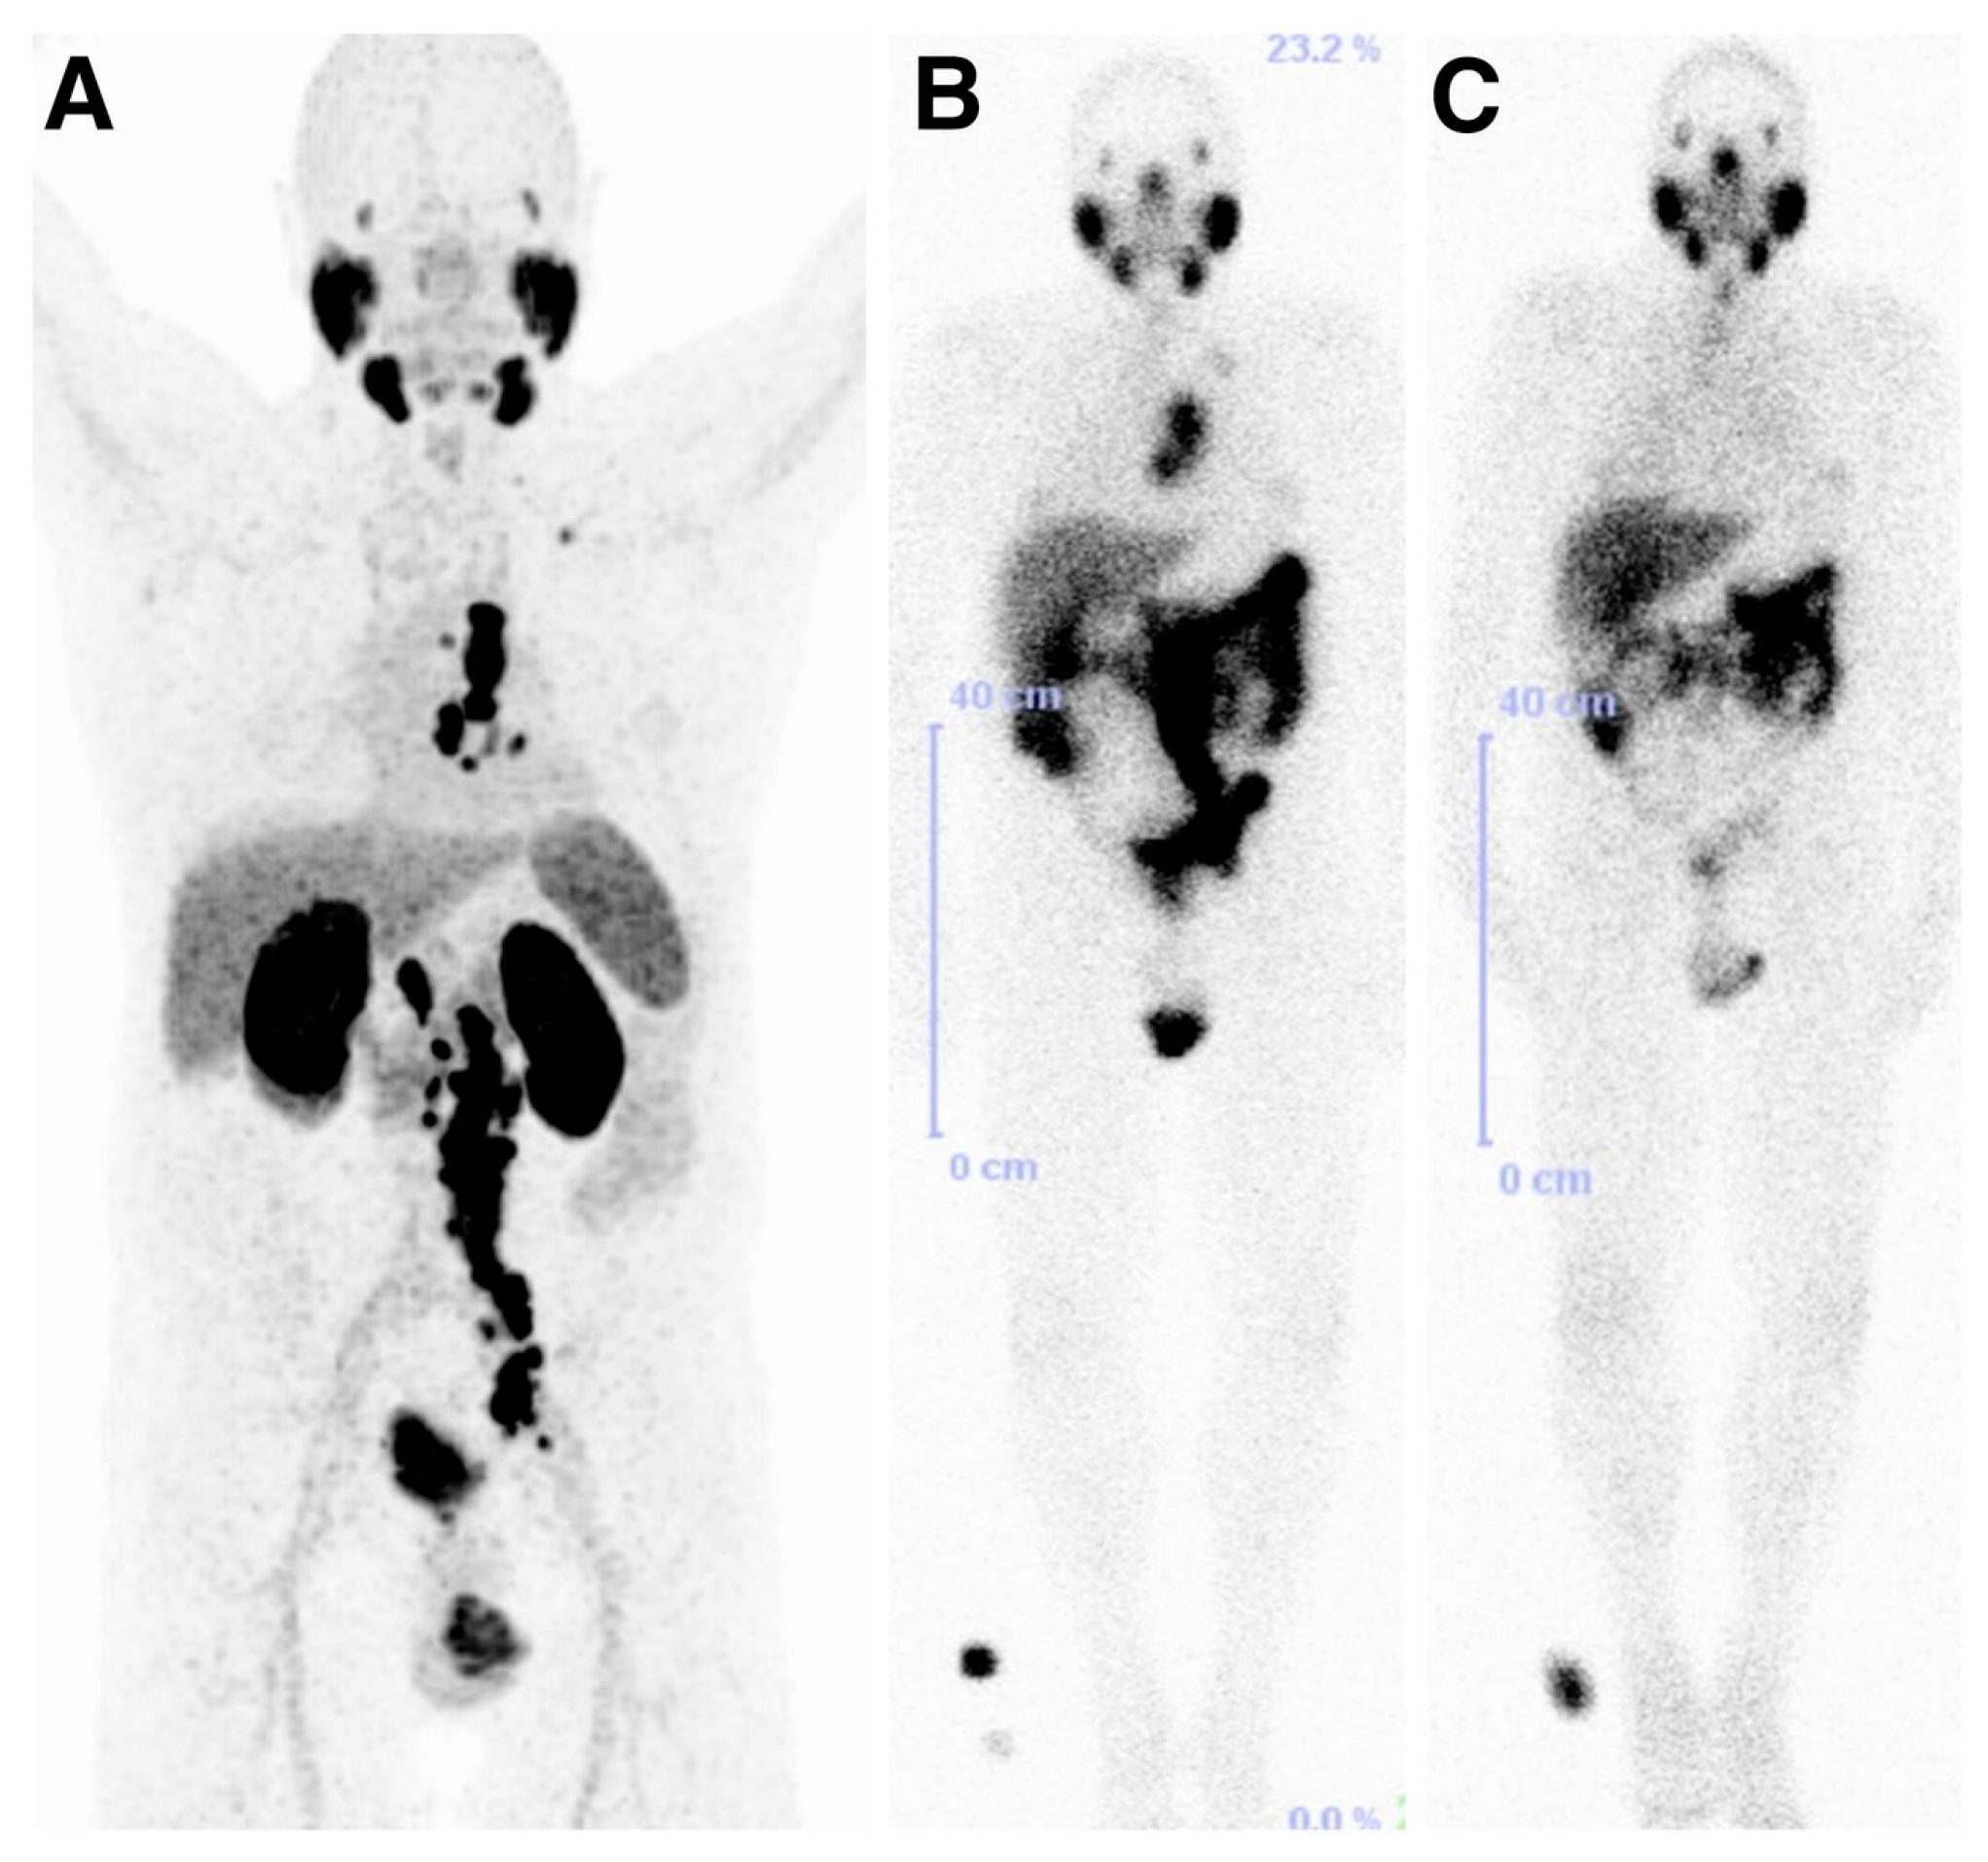

- Lawal, I.; Vorster, M.; Boshomane, T.; Ololade, K.; Ebenhan, T.; Sathekge, M. Metastatic prostate carcinoma presenting as a Superscan on 68Ga-PSMA PET/CT. Clin. Nucl. Med. 2015, 40, 755–766. [Google Scholar] [CrossRef] [PubMed]

- Soydal, C.; Ozkan, E.; Yerlikaya, H.; Utkan, G.; Kucuk, O.N. Widespread metastatic prostate carcinoma shown by 68Ga-PSMA PET/CT. Clin. Nucl. Med. 2016, 41, 294–305. [Google Scholar] [CrossRef] [PubMed]